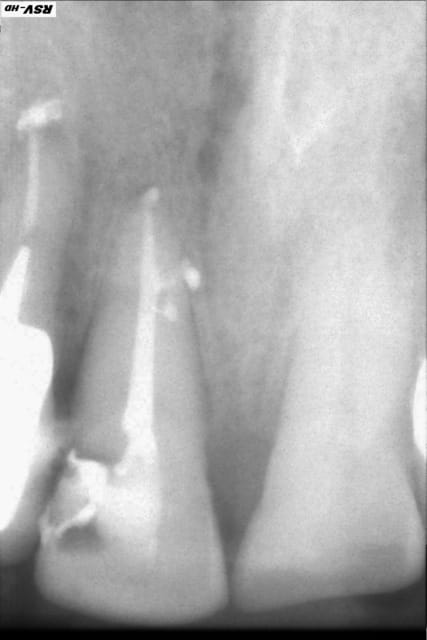

Petite endo bizarre...

Endo 17  2  c nes xyk9ig - Eugenol

Endo 17  3  postop iprbqy - Eugenol

Endo 17  1  preop n6m5ub - Eugenol

très propre